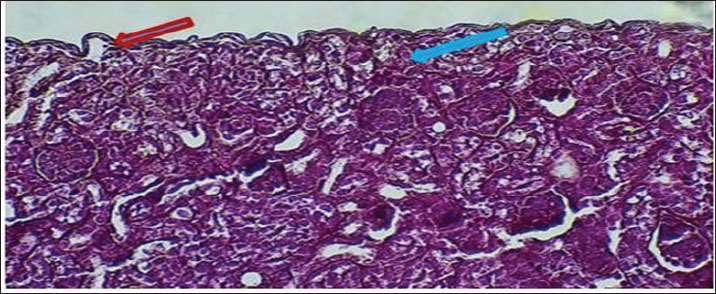

The fundamental unit of kidney structure and function presented in the Introduction was the nephron, which was a combination of the glomerulus, proximal convoluted tubule, loop of Henle, distal convoluted tubule, and collecting duct. When stained with hematoxylin and eosin, the low-power study of Fig. 1 marks off two regions in the kidney: the cortex on the outside and the medulla on the inside. The thin connective tissue capsule encompasses the cortical area on the outside of the structure (at the blue arrow). The renal cortex holds renal corpuscles and some tubules, but the interior appears mostly tubular because it consists of Henle collecting ducts and loops. One can observe renal corpuscles, which are marked by visible Bowman’s capsules, as indicated by a yellow arrow. In Figure 2, Alcian blue staining shows the renal cortex in the 40x section and proximal and distal convoluted tubules. The simple cuboidal epithelium (indicated by red arrows) on the tubules is a special feature of early postnatal development. Near the corpuscle, glomerular arterioles (blue arrows) grow to aid blood circulation. Using the Alcian stain, glycosaminoglycans located in basement membranes and the extracellular matrix are visualized, and this helps make epithelial cells more noticeable. In Figure 3, the Masson’s Trichrome-stained picture at 10x showed how the kidney’s connective tissue is organized. A thin layer (marked with the red arrow) made of fibers surrounds the organ, giving the tissue a blue-green color because of the collagen. In Figure 4, the section from the 1-week shows images of both H&E staining and Alcian blue staining of the ureter cross-sections. The ureteral lumen is small throughout and runs in the center (pictured by the red arrow). On the inside, there was a small layer of squamous epithelial cells (yellow arrows) and a thin layer of muscle envelope (blue arrows) essential for making urine flow. Alcian blue mucopolysaccharides were found in the epithelium and the space below, suggesting that the mucosa was developing at the beginning of the week. In Figure 5, two 40x showed the ureter stained with PAS and Masson’s Trichrome. The yellow arrow shows the epithelial layer, the blue arrows show circular smooth muscle fibers, and the red arrow shows the longitudinal muscle layer. The outer layer is indicated by the black arrow. The Masson stain in panel B highlights the shape and layers of the smooth muscle, where collagen fibers are shown in blue and muscle cells are shown in red to clearly display the early development of the ureter.

Figure 6 shows that the maturation of kidney tissue was visible on the later low-power H&E section of the 2-week-old hamster kidney compared with the 1-week specimen. The red arrow indicates how the renal cortex parenchyma is arranged, and the tubular regions are increasingly gathered and distinguished. Because the glomerulus was better developed, there was a clearer and bigger outline of the renal corpuscle. The yellow arrow marks the tubules that have been collected, and they now have distinct profiles and clear lines between epithelial cells, showing that urine concentration is starting and nephron structures are also dividing further. Figure 7 (Section Masson) implies that the capsule of the kidney cortex has received more fibrous support than in the previous stages. Columnar epithelial cells (marked by the blue arrow) were longer and better arranged in the inner part of the sac than they had been a week ago. The red or pink epithelial layer and the cytoplasmic structure were clearer from the blue collagen, indicating the formation of different tissue compartments in the body. Figure 8 presents the appearance of a hamster’s ureter at 2 weeks, stained with H&E in Figure A and with Alcian blue in Figure B at both 10x and 20x magnification. The lumen (red arrow) was slender and surrounded by a better-defined epithelial lining in both images. Simple squamous epithelial cells are marked by the yellow arrow in the transitional epithelium, and the blue arrow indicates a smooth muscle layer below. Mucosubstances in the epithelial layer became more noticeable in panel B because the Alcian blue stain was used, suggesting more mucus secretion for passing urine and shielding the bladder wall. Figure 9 includes two histological images of the renal cortex of a 3-week-old hamster. One was stained with hematoxylin and eosin (A) and the other with Masson’s trichrome (B) under 40x magnification. There was an increased formation of renal corpuscles in every area, where the capillary tufts were evident (yellow arrows). The red-marked proximal tubules have a well-formed brush border, and their cytoplasm is colored eosinophilic. Both images have blue arrows that confirm that the renal veins were connected with the blood vessels in the cortex. In Fig. 10, Panels A and B, Masson’s Trichrome (A) and Van Gieson (B) stains were used for transverse sections seen at 20x. The red arrows show where the unambiguous ureteral lumen was located. Simple squamous epithelium was highlighted by yellow arrows and stratified. The blue arrows denote the muscles found in the area, whereas the black arrow in panel B marks the pink layer seen on the outside called the serosa. Currently, the ureter looks complete, as confirmed by its multilayered structure, and is ready. Fig. 11 shows the renal cortex from a 2-month-old hamster stained with PAS (A, 20x) and H&E (B, 40x). Panel A shows that the renal capsule is organized and composed of fibrous tissue. The yellow arrow indicates that the advanced renal corpuscle has a distinct Bowman’s space, and the blue arrow indicates a major proximal tubule marked by its brush border and PAS-positive basement membrane. The black arrow indicates the wider lumen and the pale cytoplasm of the distal tubule. In the H&E image, the two main kinds of tubules were easily identified, proving that the nephron has developed completely and matured in the cortex. At a magnification of 40x, the renal corpuscle is clearly seen in Masson’s Trichrome (A) and Van Gieson (B) stained slides, as shown in Fig. 12. The blue arrows show complete glomerular capillaries that were properly perfused and assigned a consolidated mesangial matrix. These arrows were aimed at the juxtaglomerular cells on the vascular side, indicating that they were ready to release renin. The red arrows show the urinary pole and the proximal tubule entrance, indicating that the nephron was intact. The black arrows indicate sections of the tubules that lie far from the glomerulus. They also highlight how the nephron is made up of important sections and how the corpuscle becomes an effective filtration unit. Fig. 13 shows a sliced ureter in a 2-month-old hamster demonstrating that its structure was fully mature by Masson’s Trichrome (A) and Van Gieson (B) staining. The red arrows show a wideness to the ureter, proving that the epithelial and muscular layers have healed well. The yellow arrows point to a fully developed urothelium and show simple squamous to cuboidal features according to the ureter location. The thicker and more organized circular muscle groups were observed, where the blue arrows were found inside the walls.

Fig. 6. Cross-hematological sections of kidney hamsters aged 2 weeks showing cortex parenchyma tissue (red arrow) and renal corpuscle (blue arrow) collected tubules (yellow arrow). 10x. H&E.

Fig. 7. Cross-section of kidney cortex at 2 weeks of age showing two layers of connective tissue capsule (red arrow) and sub capsular simple columnar epithelium (blue arrow). 20x. Masson’s trichrome stain.

Fig. 8. Cross-histological section of the ureter in hamsters aged 2 weeks showing a mild lumen (red arrow) in the middle, simple squamous epithelial (yellow arrow), smooth muscle A-10x H&E stain B- 20x. alcian blue.

At 1 week of age, the kidney of the hamster showed typical signs of early postnatal development, such as a defined renal capsule, not so mature renal corpuscles with narrow spaces where blood fluid was processed, and the inner tubule walls were mainly made up of simple cuboidal cells. These results showed that in rodents, development of the kidney glomerular and tubular structure continues shortly after birth, serving the kidney’s maturation (Kose et al., 2020). Indeed, the thin connective capsule seen on both H&E and Masson’s Trichrome stain indicates that mesenchymal cells are already dense, and this observation fits with what has been found in developing rodent species, where the renal capsule becomes thicker and starts changing by the second week after birth (Singh et al., 2022). A hamster kidney has renal corpuscles with a narrow space for forming urine, and the Bowman’s capsule is less developed, indicating that glomerular growth in the hamster has just begun. These observations are consistent with previous findings on neonatal rats and mice that the kidneys’ filtration ability was limited during the first week of life (Lee et al., 2019). Observing articular arteries near the glomeruli is essential because it represents vascular recruitment that supports the continuous creation of blood vessels in the developing kidney tissue (Chou et al., 2021). In addition, Alcian blue staining confirmed the presence of acidic glycosaminoglycans in the basement membranes, which is an important early indicator of nephron development and the formation of tubule centers in epithelial cells (Sajjad et al., 2020). The appearance of Henle’s loops and collecting ducts on slides with PAS and Van Gieson stains shows that urine was being concentrated at this point, albeit only to a small extent in the renal medulla. As Zhang et al. (2023) described in their study, the simple squamous epithelium found in the thin limbs of Henle’s loop in neonatal rodents was a sign that the structure was immature and unsuitable for effective countercurrent exchange until the third postnatal week. In addition, the PAS stain revealed cells that looked like zymogens, which might match immature tubular epithelial cells that were not yet fully differentiated (El-Mahdy et al., 2019). Postnatal growth and development in the ureter were observed after H&E, Alcian blue, PAS, and Masson’s trichrome staining. The fact that the lumen was narrow and surrounded by a simple squamous epithelium, along with the emergence of a double layer of smooth muscle tissue, suggests the initiation of peristalsis. In newborn rats, smooth muscle development occurs in the late fetal stage and continues after birth to form the two muscle layers (Matsumoto et al., 2020). At this point, Alcian blue detected in the ureter confirms the presence of mucopolysaccharides that could help protect the lumen and make the tract more flexible (Ishak et al., 2022). It could also show early formation of the stromal matrix in the capsule and interstitium by finding collagen fibers during Masson’s trichrome staining. It is essential to keep the structure of the kidneys intact and to attach the nephrons. Wu et al. (2021) revealed a similar behavior in the kidneys of newborns, as increased collagen types I and III are seen during the first postnatal week, and these help form tubules and stabilize blood vessels. At 1 week of age, the hamster kidney and ureter are changing from a prenatal structure to a fully functioning one. They confirm what has been found in mice and improve the development of the kidneys and ureters in hamsters, a major animal used in renal medical studies (Al-Rubaye et al., 2018; Kim et al., 2024). The 2-week observations revealed that both glomeruli and tubules were maturing and specializing in the kidney. The cortex appears thicker, has more cells, and the parenchyma is organized more clearly in these structures. Bowman’s capsules were thicker, and the renal corpuscles were also more formed. Important changes in the kidney, including elongation of podocyte foot processes and growth of glomerular capillaries, occur between days 10 and 15 after birth (Abdel-Rahman et al., 2020). The presence of PAS-positive material in the capsule and basement membranes of Bowman’s capsule is another indication of glycoprotein accumulation during postnatal kidney development. The renal corpuscles stand out with their unique build and know-how of filtering blood. A further examination in neonatal Wistar rats indicated that the parietal epithelial cells depositing more extracellular matrix material caused the thickening of the Bowman’s capsule during the second week postbirth (Salem et al., 2021). Zymogen-like cells in the proximal tubular epithelium might start the development of enzyme creation, as it was shown in rabbit and guinea pig kidneys when renal tubules are starting to differentiate (Zahra et al., 2019). The medullary region contains vertically arranged, straight tubules that are covered by simple columnar epithelium. They probably represent the early part of the collecting ducts and the thick parts of the ascending limbs. Setting up the renal structure in this manner was necessary to develop the main renal countercurrent system. These developments in medullary extensions and epithelium were in line with the explanations provided by Balasubramanian et al. (2018), who said that they boost both sodium reabsorption and urine concentration in rats beginning on day 14 after birth. In this process, the Van Gieson stain enables the maturation of the renal tissue and supports the correct placement and stability of nephrons. There were more layers in the renal capsule, indicating the readiness of the tissue to handle the increased blood pressure in the artery. In Syrian hamsters and tree shrews, the renal capsule thickens with fibroblasts and collagen I during early growth, acting as added protection from trauma (Nasr et al., 2023). The better organization of subcapsular nephrons indicates that nephrogenesis is very close to finishing—a stage usually completed at the end of the second week in most rodent models (Barakat et al., 2019). When viewed under Alcian blue staining, the transition zone of the ureter has several cell layers and exhibits heavy accumulation of mucus. The muscularis muscle layer develops into circular and longitudinal bundles to allow regular urine movements. A study on mouse postnatal ureter development found that muscle cells begin to contract with coordination once the tube’s layer and inner lining have been completed on Days 10–18 (Farag et al., 2022). The widening of the ureter’s lumen, which was observed in slices stained with hematoxylin and eosin and with PAS, also demonstrates the organ’s readiness for more renal urine. These results indicate that on postnatal day 14, there were significant changes in the glomerular, tubular, capsular, and ureteral structures of the kidney and ureter. As a result, these changes ensure that vital filtering, reabsorption, and elimination functions are available for self-control of the body, as backed up by studies of several rodents and ensuing histological and ultrastructural sessions (Al-Khafaji et al., 2020; Alshammari et al., 2023). When the Alcian blue stain was positive, mucopolysaccharides were still being produced for the protection of the urothelium, and when PAS staining was present, it indicated that the basement membrane had grown and differentiated properly. In hamsters, the kidneys show significant improvement at 3 weeks after birth as the renal corpuscles, proximal tubules, and blood vessels can be easily distinguished. Mature glomerular tufts and an increase in the size of Bowman’s spaces which was clearly observed by Masson’s trichrome dye staining. Similar to 17- to 21-day-old mice and Mongolian gerbils, this same order of development is typical for nephron maturity and glomerular capillaries in rats (Al-Dosari et al., 2021). Clear brush borders in the proximal convoluted tubules show that the kidneys have achieved a significant absorptive function, reflecting the situation in rodent models (Saleh et al., 2023). PAS-stained cortex reveals that the capsule and widespread tubules are clearly visible. This suggests that the blood vessels were being organized and the tubular alignment was increasing. In the striated distal segments, the PAS-positive reaction indicates that more basement membrane proteins were present, which enhanced ion movement and strengthened the tubules while reabsorption was going on (Okasha et al., 2022). Similar to previous research in gerbil and hamster models, the so-called regenerating zone shrinks around the third postnatal week, indicating that nephron growth is finished and the last maturation phase begins (Abbas et al., 2021). The glomerular structure was stained using Van Gieson stain to clearly separate the layers of Bowman’s capsule, visceral, and parietal. Evidence from previous studies was confirmed by the presence of red collagen in the capsular region, indicating that extracellular matrix deposits are important for stabilizing kidney growth after birth (El-Taher and Mahrous, 2020). In addition, the structure of the organized capillary beds and division of glomerular layers corresponds to the time when podocytes and endothelial cells were fully matured in week three (Mekawy et al., 2020). The ureters have a wider, healthier lumen, and their epithelium and muscle layer components were clearly differentiated. The ability to distinguish circular from longitudinal smooth muscle fibers using Masson’s trichrome and Van Gieson staining is important for the development of peristalsis in the intestines. Similar muscle changes peak between days 18 and 24 in the postnatal rats’ ureters, helping them send urine easier (Mohammed et al., 2022). On the histochemical side, the epithelium was seen to store mucopolysaccharides using Alcian blue staining, and the basement membrane was fully developed according to results from PAS staining in the image. At this point, the urothelium showed glycoconjugates because the mucosal barrier was strengthened, a finding that resembles results from a rabbit study where the study saw increased mucin in response to an increasing urine osmolarity (Kamal et al., 2021). Also, the reactivity to PAS confirms that the urothelial cells have stabilized and developed into the right type of cells, just as was observed in other rodent kidney–ureter studies conducted after birth (Shaker et al., 2023). By 3 weeks, the kidney and ureter of the hamster have developed almost fully, as indicated by laboratory findings and what has been observed in other mammals. Such changes were an indicator that the tissue was shifting to performing its basic functions, involving more detailed cell divisions, a rise in blood vessels, and remodeling of the supporting structures (Younis et al., 2022). At 2 months, the nephron structure, found in the renal cortex, was mature and included in each renal corpuscle as well as the proximal and distal tubules. In these pictures, the renal corpuscles appear compact; there is a clear space around the Bowman’s capsule, and the tubules are easily visible. The presence of PAS-positivity in the proximal tubules indicates that the basement membrane is fully mature, has an abundance of glycoproteins, and aids in maintaining the correctness and selectivity of reabsorption (Zhou et al., 2021). It was obvious from the stain that the proximal cells have denser cytoplasm, while the distal ones have widened lumens and mildly stained cytoplasm due to their function in salt and water reabsorption (Chen et al., 2020). The vascular pole contents indicate that the renal corpuscle has grown and is ready to work. The juxtaglomerular apparatus yellow arrows helps regulate the body’s blood pressure and control the rate of filtration through the launch of renin. It has been noted that the morphology of juxtaglomerular cells in rats matures and they can react to major signals in the body by weeks 6–8 (El-Nahas et al., 2019). In addition, both Masson’s and Van Gieson in panels A and B accentuate the clearly defined system of fibers around the glomerular capillaries, which stabilizes the matrix and shows normal endothelial-mesangial relations in older rodents (Ahmed et al., 2021). The ureter had a large lumen, a well-structured epithelium, and smooth muscle groups. Because the eggfish’s structure has a distinct circular layer, a longitudinal layer, and a thick serosa, it can perform complex contractions. This was in line with the observation made by Azzam AM Ismail and Khalil (2022), who said that the ureter was fully developed and starts contracting and moving in waves to help empty the bladder in rats that were no longer nursing. Many layers in the smooth muscle make it possible for the ureter to propel and smoothly modulate fluid. The epithelium has squamous features and keeps its junctions intact, whereas the smooth muscle layers become thicker and are divided into segments. In panel B, green arrowed perivascular adipose tissue was found around the ureter, which enhances this region’s ability to get nutrients and was present in adult mammalian ureters to support their functioning (Talaat et al., 2020). The reactivity with Alcian blue and PAS showed that glycosaminoglycans were being produced continuously, helping the epithelium remain flexible and save the kidneys from exposure to dangerous urinary solutes (Salem et al., 2023). Renal and ureteral changes appear at this age because the organs have finished their development. Lab discoveries in rodents show that the structure and function of the nephron and collecting system resemble those of an adult around 6–8 weeks after birth (Mostafa et al., 2022). This information about the maturation of fast golden hamsters could give more insight into their usefulness in nephron and urological studies. Further elaboration has been given on the significance of glomerular and tubular development maturation. The development of glomeruli is critical for the development of an effective filtration barrier because the formation of podocyte foot processes and capillary loops directly increases glomerular filtration capacity. Likewise, proximal and distal tube maturation is essential for reabsorption and secretion to achieve electrolyte and fluid balance. These structural changes ensure that the kidney functions as a homeostatic organ when it reaches adulthood. The results of the current research correspond with the prior observations in rodents, which revealed that immature glomeruli and undifferentiated tubular epithelium make immature kidneys unable to filter as well (Lee et al., 2019; Kose et al., 2020). Bowman capsule progressive thickening and tubular epithelial differentiation occurred as previously described in rats, hamsters, and gerbils during the second and third postnatal weeks (Abdel-Rahman et al., 2020; Abbas et al., 2021). These comparisons indicate that the structural maturation in golden hamsters is similar to that in other rodent models and that nephron development is important in determining normal renal physiology. Our further work intends to use this study to investigate the molecular pathways in renal and ureteral development with high-order histochemical and immunohistochemical procedures that could give us a deeper insight into this subject pertinent to the fields of veterinary and biomedical sciences.